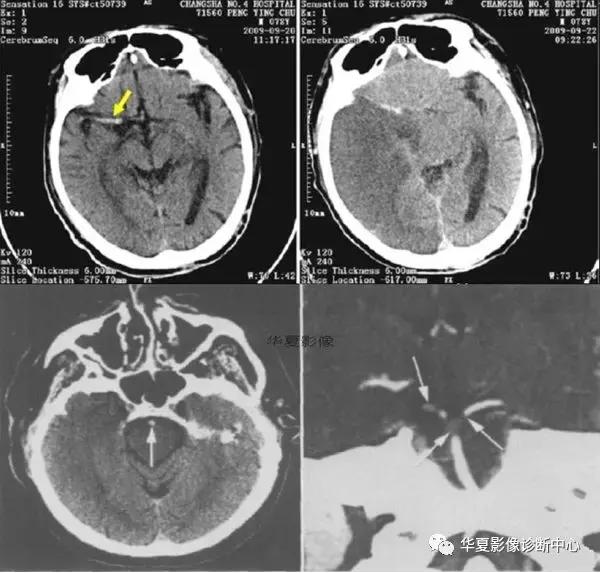

四、脑血管高密度征

此征可出现在颅内任何动脉、甚至静脉,是CT平扫动脉闭塞的早期直接征象,代表血栓形成或栓塞,对脑梗死的早期诊断和指导治疗有一定的意义。脑动脉高密度征最常见的为大脑中动脉高密度征(HMCAS),其次是基底动脉高密度征(HBAS)。这是因为大脑中动脉(MCA)血栓形成或栓塞引起的脑梗死最常见,占脑梗死的一半左右。另外这些动脉走行区有脑脊液,增强了组织间对比。应该指出脑动脉局部、非对称性高密度是早期脑梗死的可靠征象,若两侧动脉对称性密度增加,血栓栓塞的可能性小。HMCAS脑梗死多呈非对称性高密度征,多发生在MCA第1段和第2段,发生在第2段呈“圆点征”或“破折号征”。有文献报道非对称性HMCAS提示血栓栓塞准确度16%~64%不等。大脑前动脉和大脑后动脉血栓栓塞并动脉粥样硬化性疾病,沿血管壁或动脉腔内出现密度增加的粥样斑块;部分斑块出现钙化,CT值可达97~221HU,可能是导致脑动脉高密度征假阳性的原因之一。从理论上讲,若正常动脉周围为透光区,正常的血管可显示为高密度,尤其在脑底部走行于低密度脑脊液中的动脉。因此动脉腔内高凝状态(平均红细胞比容增高,在高血压和糖尿病发生率高)引起动脉表观密度增加或邻近脑组织密度减低(如脑水肿),也可能导致脑动脉高密度征假阳性的出现。也有人指出脑动脉高密度征出现原因可能是正常、或高凝血状态或血管壁的微钙化、邻近脑组织低密度等。因此脑动脉高密度征患者还应有脑区域梗死证据。另外,脑动脉高密度征还可见于蛛网膜下腔出血、脑萎缩、脑白质疏松症、血管神经性头痛和神经*能官**症等。因此,需严格掌握脑动脉高密度征的诊断标准,能否成为早期溶栓治疗指征,应密切结合临床来决定。脑动脉高密度征的检出率与检查时间以及CT的分辨力有关。脑动脉高密度征可能是短暂、一过性现象,在发病早期HMCAS阳性率较高。有报道脑梗死发病后90 min可见到脑动脉高密度征,但也有作者认为在发作时即可见到脑动脉高密度征。HMCAS消失的原因一般认为是血栓溶解或逐渐演变成等密度。另外层厚和CT分辨力也与HMCAS检出率有关。层厚越薄,越容易发现。脑动脉高密度征是脑梗死最早期征象之一,可是否能作为溶栓和判断溶栓效果的指标,还存争议。多数研究认为,HMCAS与脑梗死临床表现严重程度密切相关,HMCAS阳性患者较阴性者死亡率高,易出现大梗死灶、严重脑水肿、颅高压,较少患者完全康复和留下轻微后遗症。有些报道HMCAS阳性6h内用溶栓治疗比传统治疗预后明显改善;也有人认为MCAS特异性太低,不能作为溶栓指标。另外脑动脉高密度征不仅可以评价治疗效果,更重要的是对于预后的准确判断以及可以帮助医生制订合理的治疗方案。脑梗死超早期可能仅有临床表现和HMCAS,因此,研究HMCAS预测脑梗死预后的价值显得尤为重要。总之,脑动脉高密度征是急诊平扫CT预测动脉内血栓形成和梗死发生最早和最有用的征象之一。但脑动脉高密度征并不总是代表原位血栓,在临床评价中应执行更严格的诊断标准,密切结合临床,减少可能的假阳性。

上二图示大脑中动脉中心点征,后临床均证实为大脑中动脉栓塞。下左图平扫示左侧大脑中动脉M2段5mm高密度,与脑室质密度差异不明显(箭); 下右图CTA示相应部位充盈缺损(箭)。